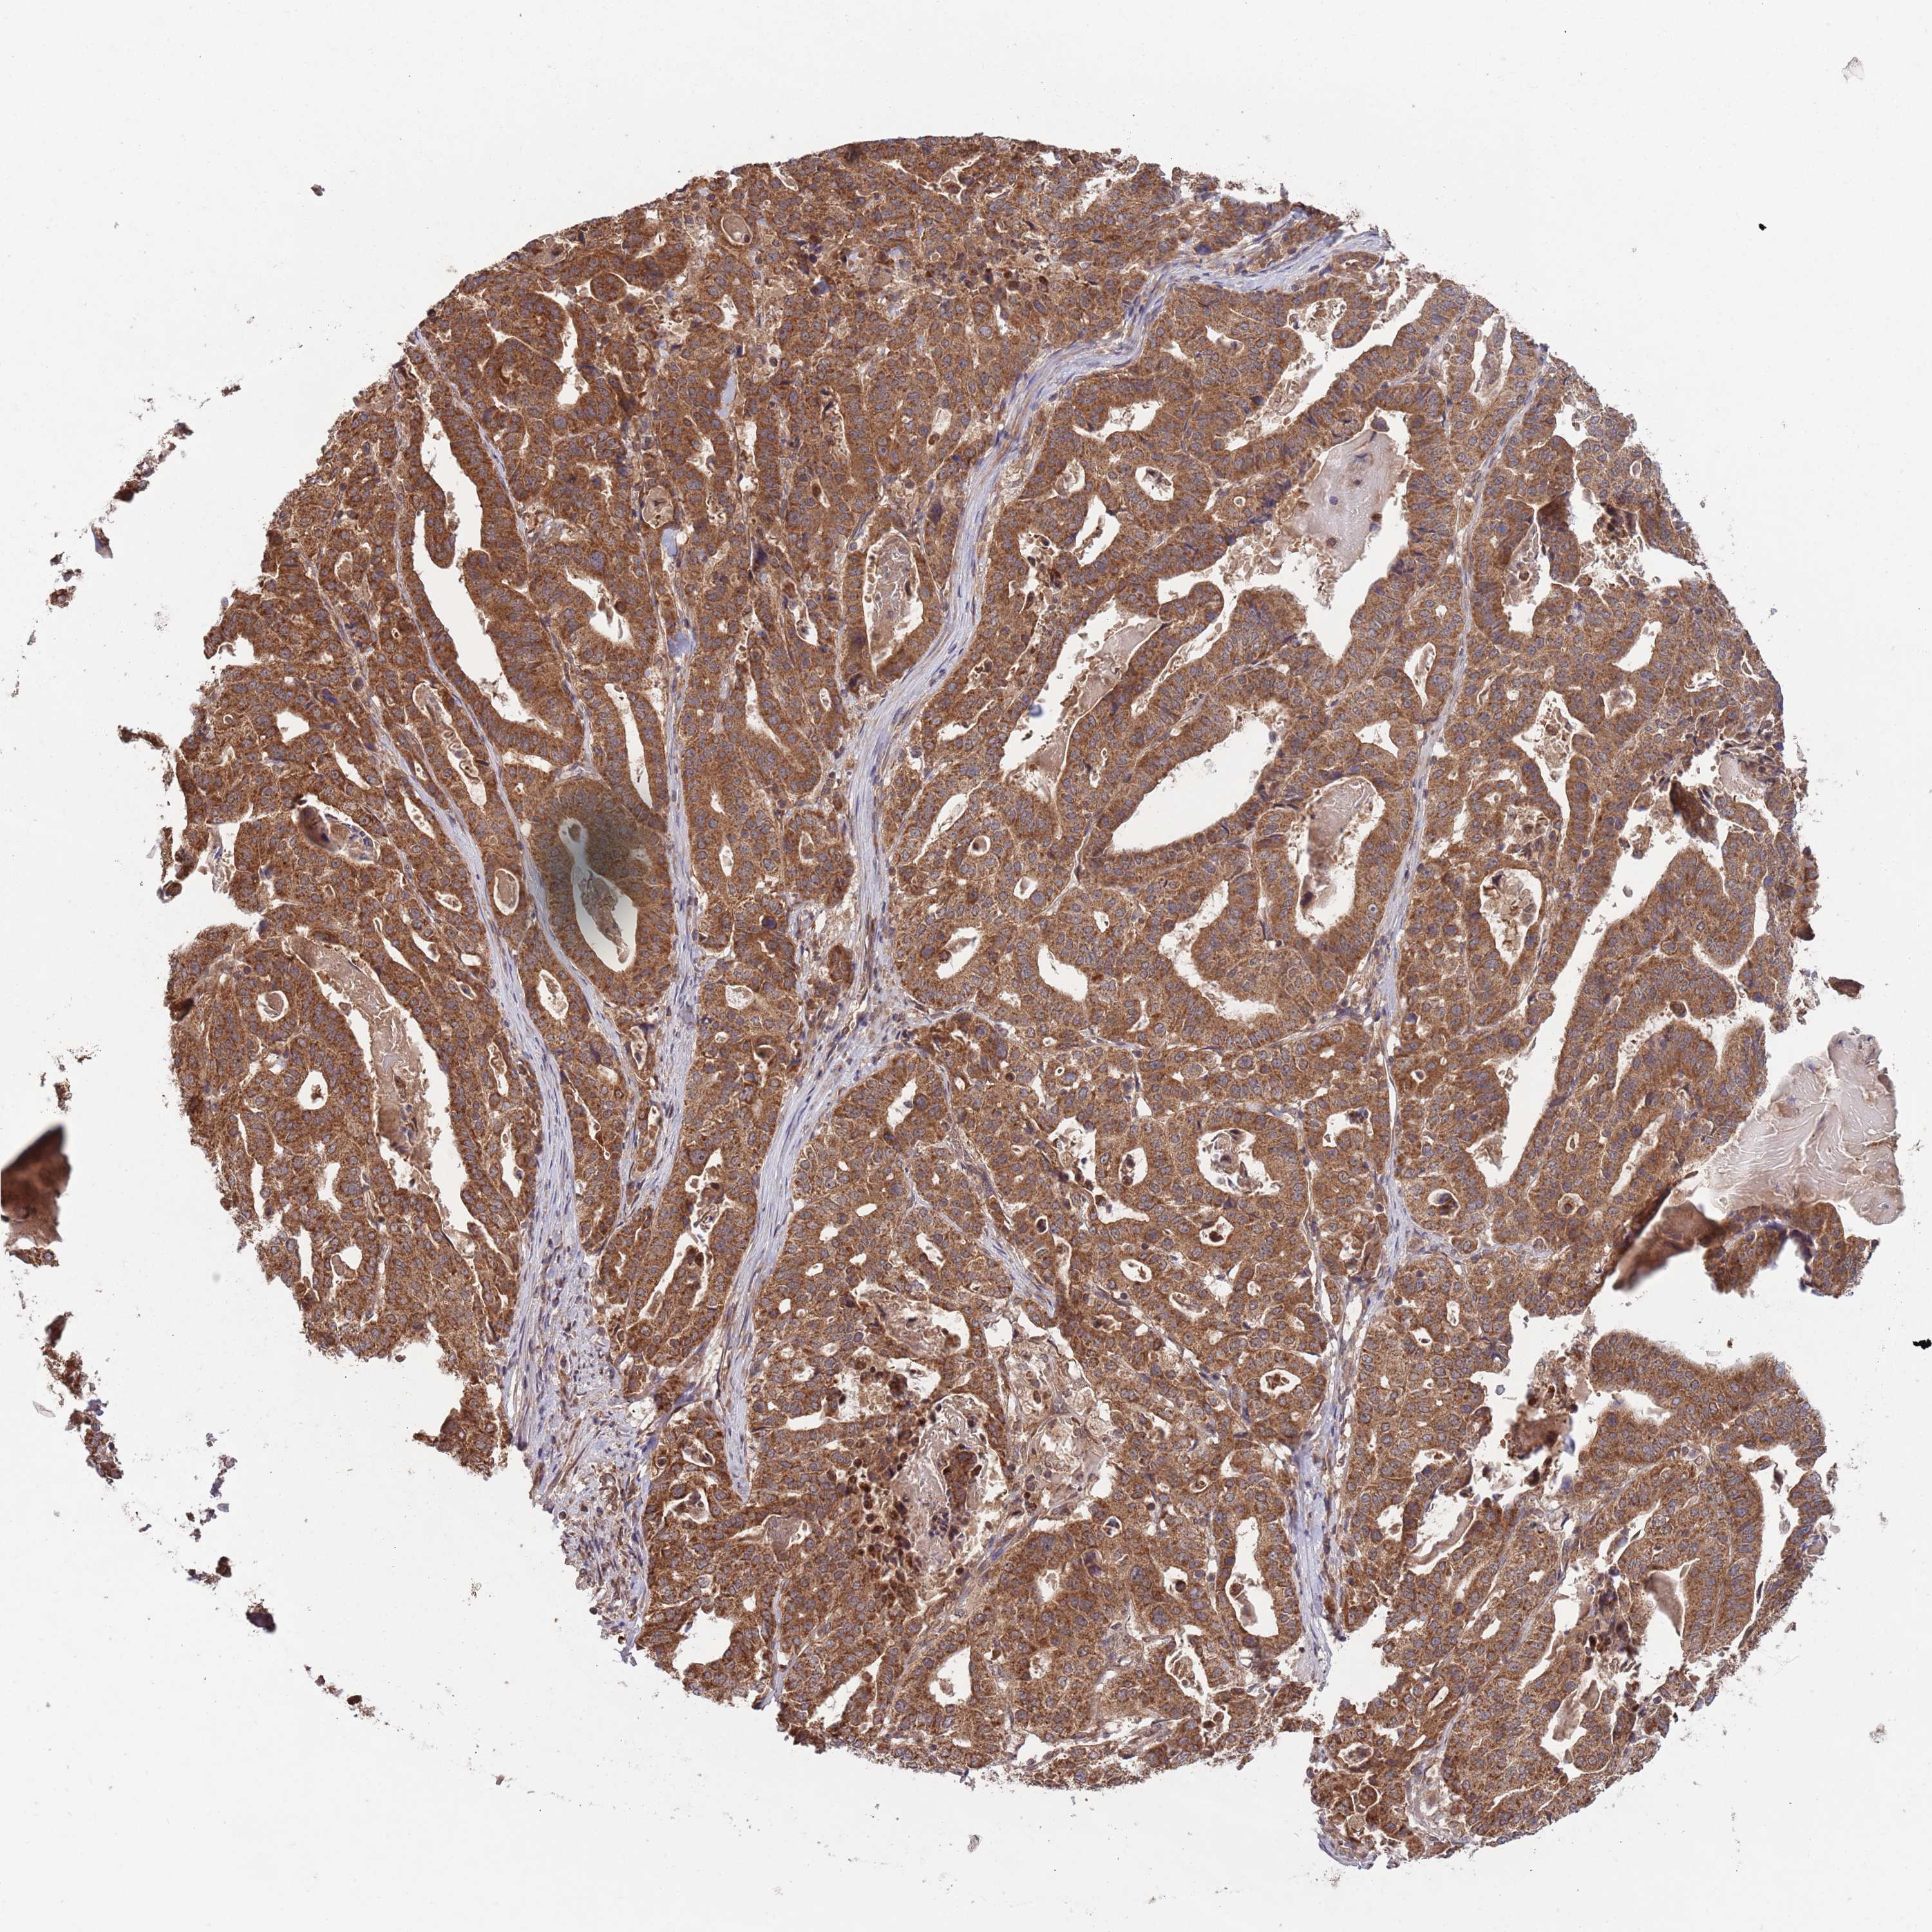

STOMACH CANCER - Protein expressioni

A mouse-over function shows sample information and annotation data. Click on an image to view it in a full screen mode. Samples can be filtered based on level of antibody staining by selecting one or several of the following categories: high, medium, low and not detected. The assay and annotation is described here.

Note that samples used for immunohistochemistry by the Human Protein Atlas do not correspond to samples in the TCGA dataset.

Antibody stainingi

Antibody staining in the annotated cell types in the current human tissue is reported as not detected, low, medium, or high, based on conventional immunohistochemistry profiling in selected tissues. This score is based on the combination of the staining intensity and fraction of stained cells.

Each image is clickable and will lead to virtual microscopy that enables deeper exploration of all samples and also displays staining intensity scores, fraction scores and subcellular localization as well as patient and tissue information for each sample.

Antibody HPA048936

Staining

High

Medium

Low

Not detected

Intensity

Strong

Moderate

Weak

Negative

Quantity

>75%

75%-25%

<25%

None

Location

Nuclear

Cytoplasmic/membranous

Cytoplasmic/membranous,nuclear

Adenocarcinoma, NOS